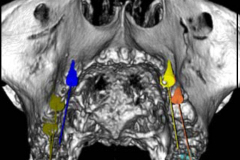

La novità principale che ha riguardato l’implantologia negli ultimi anni è l’introduzione della possibilità di effettuare diagnosi attraverso immagini tac 3D e impostare una chirurgia computer-assistita che può anche limitare l’invasività degli interventi oltre che migliorarne la predicibilità.